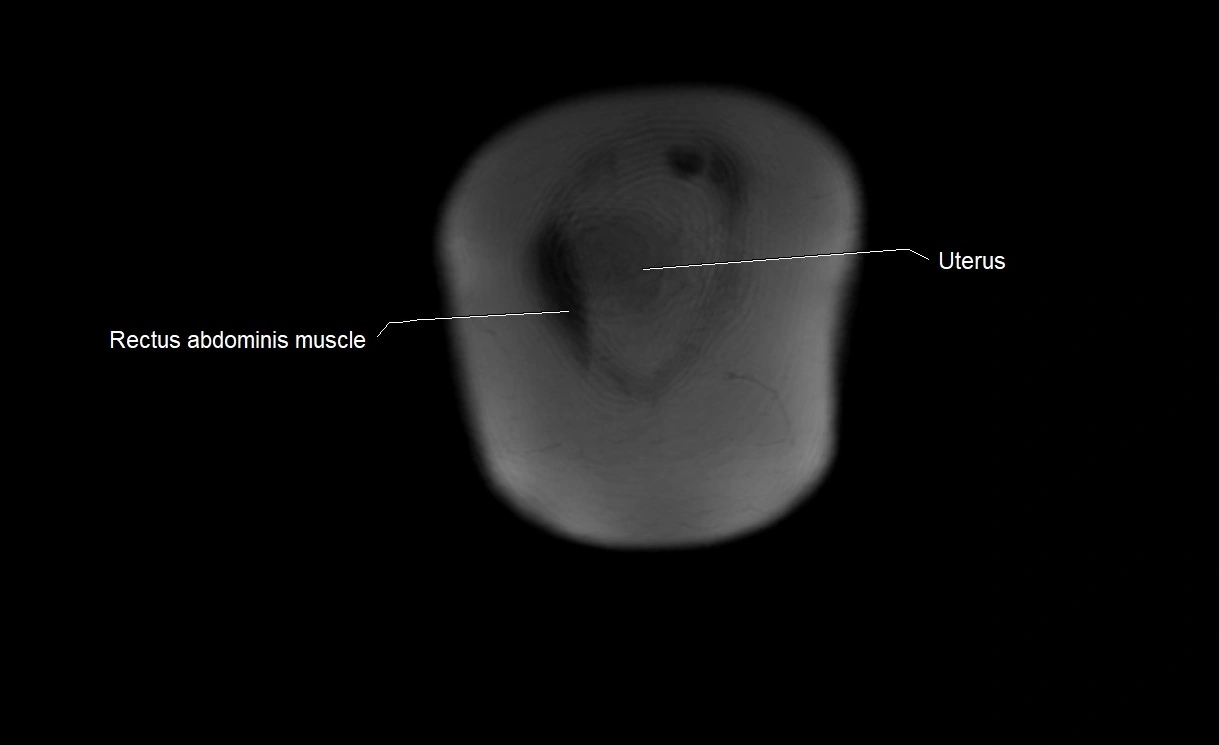

MRI Appearance

T2 HASTE (T2 GRE):

• Amniotic fluid shows very bright hyperintense signal

• Provides natural contrast against fetus and placenta

• Small particles (vernix) may appear as scattered hypointense foci within bright fluid

MRI image

image